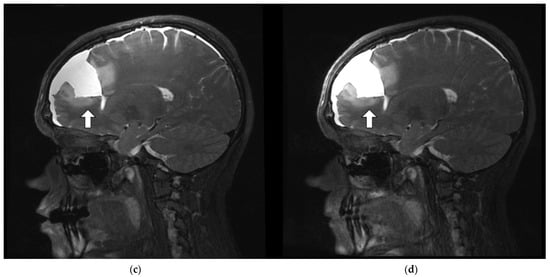

3.3.4. SNR and Anatomic Conspicuity